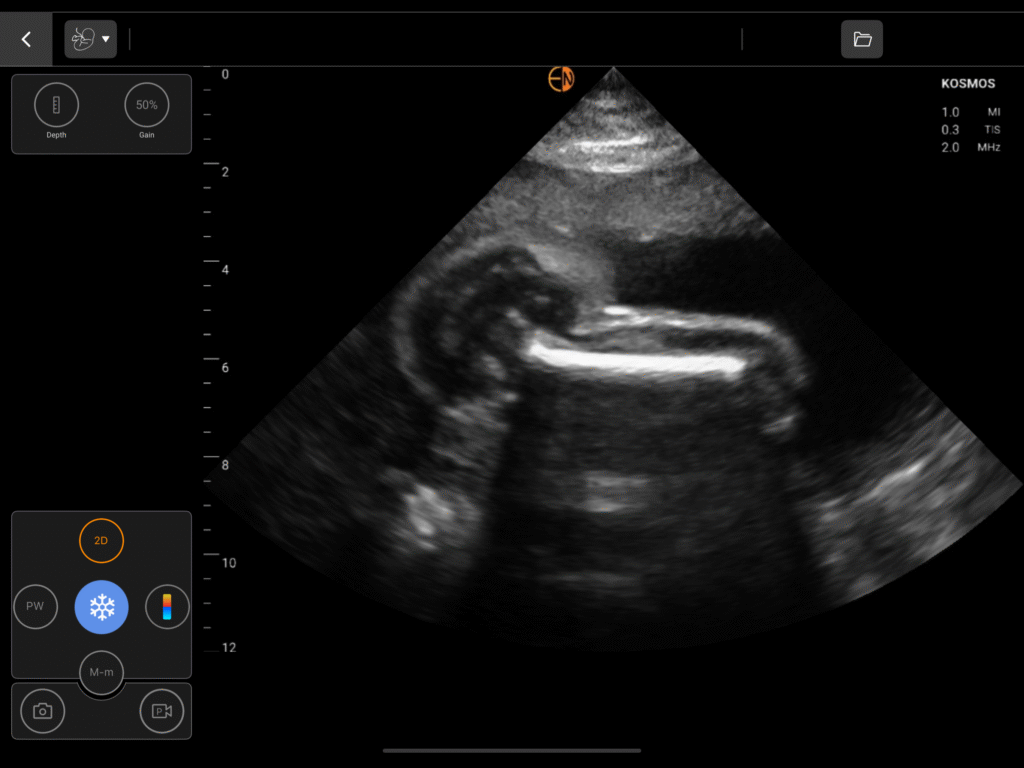

Comprehensive OB Biometry

A complete measurement and calculation package for all three trimesters, including Gestational Sac (GS), Crown Rump Length (CRL), Biparietal Diameter (BPD), Head Circumference (HC), Abdominal Circumference (AC), and Femur Length (FL).

Intrapartum Ultrasound

Assess fetal head position, station, and presentation (cephalic/breech) to guide labor management.

OB/GYN Image Gallery